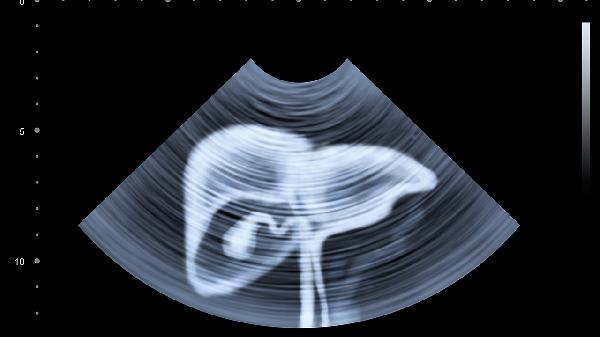

建议每年进行肝功能检查和肝脏超声筛查,乙肝表面抗原阳性者需每3-6个月复查。40岁以上人群应增加肝脏弹性检测,有肝癌家族史者需进行甲胎蛋白监测。发现转氨酶异常升高或占位性病变应及时专科就诊。